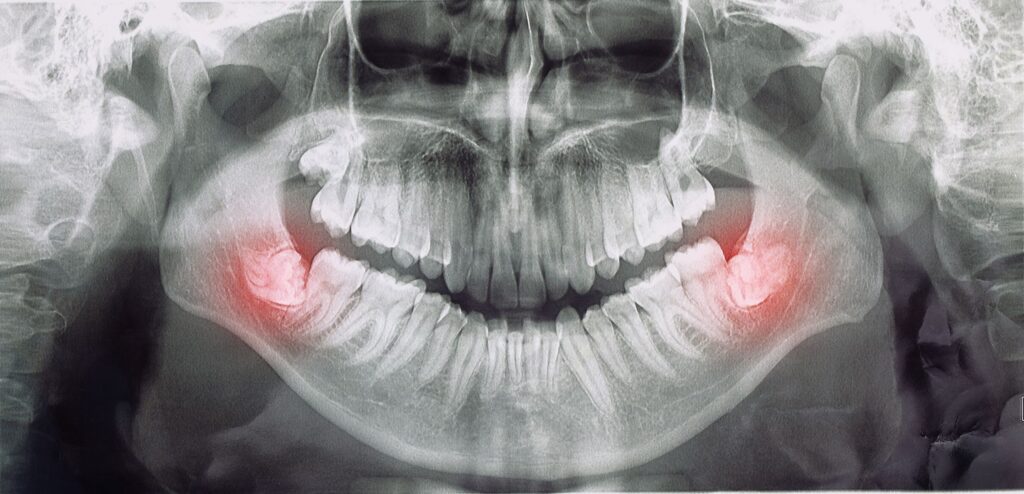

Are you wondering how many wisdom teeth you have and whether they’ll need to be removed? Only your dentist can take X-rays to see beneath the surface of your gums to let you know for certain how many there are and whether they might become troublesome. In some cases, these third molars grow in straight and there’s enough room in the jawbone to house them comfortably, so they don’t cause issues. However, if your dentist suspects they will be problematic, they’ll likely recommend an extraction.